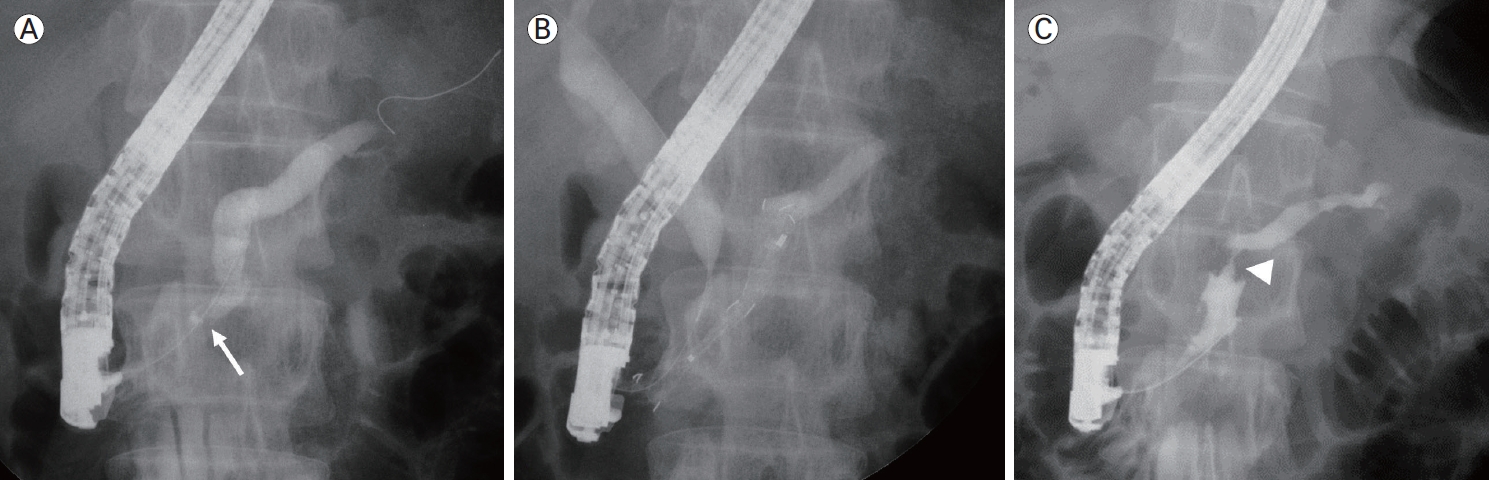

금속 스텐트를 삽입한 후 제거하였을 때 원래의 췌관 협착은 호전되었으나 금속 스텐트의 내부 끝부분에 의하여 췌관이 손상되어 새로운 협착이 발생하는 것이 보고되었다(Fig. 1) [13]. 금속 스텐트에 의하여 새로운 췌관 협착이 발생하는 것을 줄이기 위해서는 적절한 만성 췌장염 환자 선택이 중요하다. 모든 췌관 스텐트는 췌관에 변형을 줄 수 있는데[5] 금속 스텐트와 같이 직경이 큰 스텐트를 삽입하려면 진행이 많이 된 만성 췌장염 환자를 선택하는 것이 좋다. 최근의 보고[14]에 의하면 non-flared convex end를 가진 스텐트를 이용하였을 때 새로운 췌관 협착이 발생하지 않았으므로 췌관 내부에 위치한 금속 스텐트의 방사형 힘(radial force)이 너무 과하지 않도록 생각하여야 한다.

(A) Pancreatogram obtained before placement of a metal stent, showing a tight pancreatic duct stricture in the pancreatic head (arrow), associated with substantial upstream duct dilatation. (B) Successful placement of a fully covered metal stent in the pancreatic duct. (C) Follow-up pancreatogram at 3 months, showing improvement of the pancreatic duct stricture. However, a stent-induced stricture is observed at the flared end of the metal stent (arrowhead).